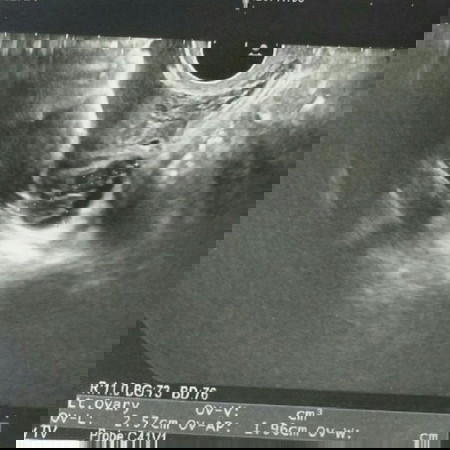

สอบถามคุณแม่ๆคะ แต่งงานกับแฟนมา 4 ปีแล้ว ยังไม่มีน้องเลย ใครมีตัวช่วยแนะนำบ้างค่ะ อยากซื้อมาบำรุงค่ะ ยิ่งตอนนี้ตรวจเจอถุงน้ำในมดลูกอีกด้วย แต่คุณหมอแจ้งว่าไม่เป็นอันตราย สามารถมีน้องได้ตามปกติ รบกวนด้วยค่าาาา ปล.เป็นรูปถุงน้ำที่เจอในมดลูกนะค่ะ